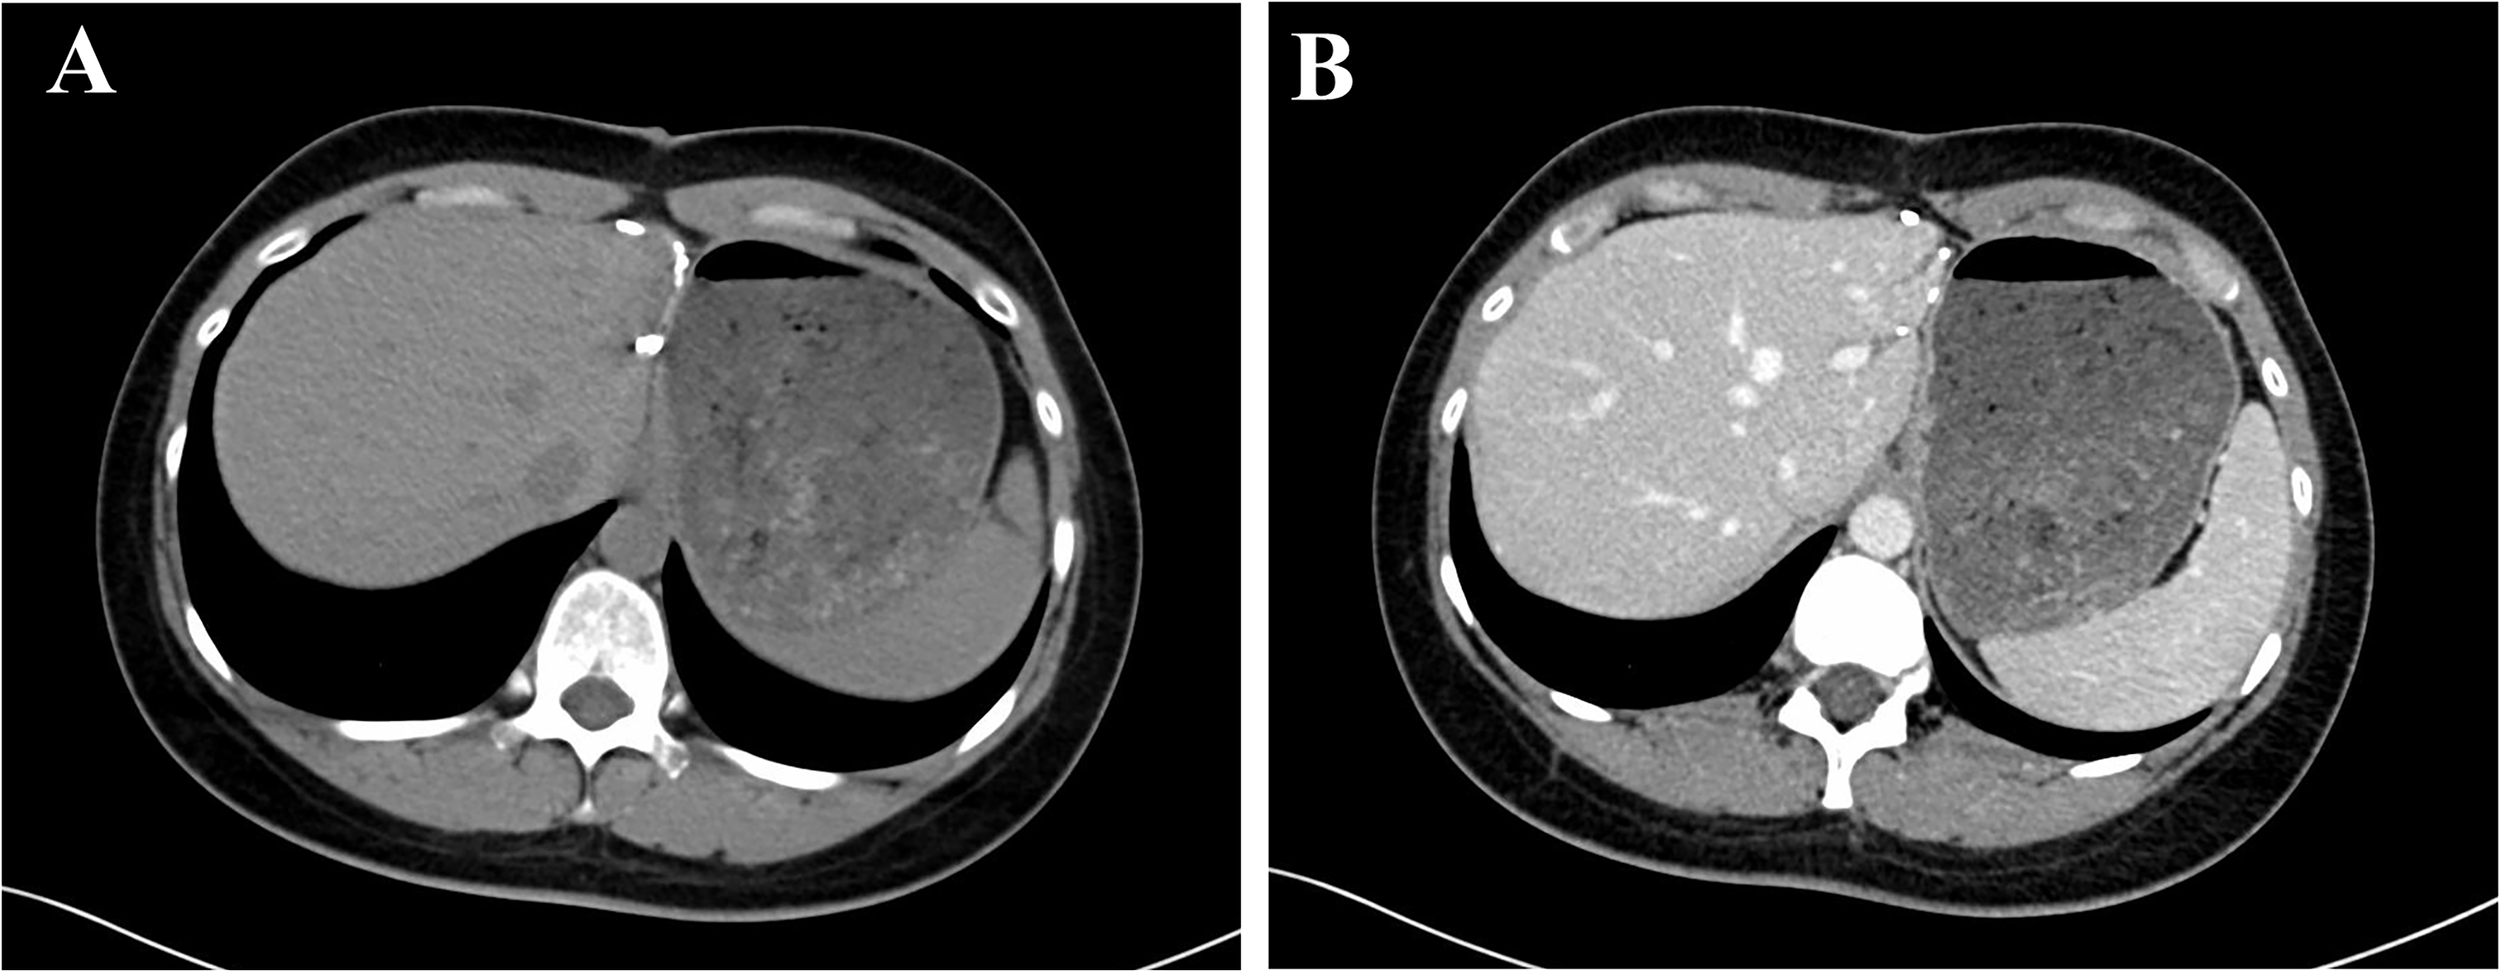

A 32-year-old Chinese female was admitted to Sichuan University West China Hospital with a 6-month history of upper abdominal pain. She denied previous radiotherapy or industrial chemical exposure. She had one previous pregnancy and and gave birth to a boy. In addition, she denied previous hormonal treatments and contraceptives. She was found to have viral hepatitis B for 6 years and had not received any treatment. Besides, she was healthy with no relevant medical or family history of diseases, such as hypertension or diabetes, and no history of smoking or alcohol consumption. Physical examination was unremarkable. A blood count showed Hb 14.2 g/dl (13–17.5), white blood cells 7.12×109/L (3.5-9.5), platelets 249×109/L (100–300), total bilirubin 12.5 umol/L (5.0-28), and AST 35 IU/L (<50). Serological testing for tumor marker of carcinoembryonic antigen (CEA) was 5.54 ng/ml (CEA ≥ 3.4 ng/ml was defined as abnormal) and hepatitis B surface antigen (HBsAg) was positive. The hepatitis B virus DNA (HBV-DNA) was less than 1×102 IU/ml (HBV-DNA ≥ 1×102 IU/ml was defined as HBV infection active), suggesting that HBV infection was inactive. The cancer antigen19-9 (CA19-9 ≥ 30 U/ml was defined as abnormal), CA125 (CA125 ≥ 24 U/ml was defined as abnormal) and α-fetoprotein (AFP≥ 7 ng/ml was defined as abnormal) was 25.6 U/ml, 13.3U/ml and 3.37, respectively. Abdominal computed tomography (CT) showed the lesion in the left lobe of liver was detected, and no tumor was detected in any other organs (Figure 1). Magnetic resonance imaging (MRI) of the upper abdomen was performed in our hospital for further diagnosis. The MRI showed a 1.1×1.3 cm lesion in the left lobe of liver, appearing low signal intensity on T1-weighted images and high signal intensity on T2-weighted images (Figure 2). Due to the similar appearance, hepatocellular carcinoma (HCC) was considered for preoperative diagnosis. The patient eventually underwent a laparoscopic liver resection of the left lobe. Macroscopically, the tumor was a yellowish solid mass with a diameter of 12mm. Microscopically, the lesion composed of undifferentiated epithelial cells with some atypical glands, and significant lymphocytic infiltration (Figure 3A). The epithelial tumor cells were featured by eosinophilic cytoplasm with large nuclei and prominent nucleoli. EBVencoded RNA (EBER) in situ hybridization was positive in tumor tissues. In addition, immunohistochemical analysis showed the lymphatic tissue positive for CD20 (B-cells, Figure 3B), CD3 (T-cells, Figure 3C), Ki-67 and negative for IgG4. Meanwhile, tumor cells positive for CK7 (Figure 3D), and negative for CK20, supporting the diagnosis of LEL-ICC.

FIGURE 1

Figure 1 The lesion in the left lobe of liver was detected on CT.

Patients monitored the disease progression at the outpatient of our hospital every 3 months in the first two years after surgery and every 6 months thereafter via blood examination, ultrasonography (US), CT, and MRI. The systematic update of patients’survival information was performed once a year. The last outpatient follow-up was in August 2022, and the tumor markers were normal. The patient was free from tumor recurrence after a 28 months follow-up (Figure 4).

FIGURE 4

Figure 4 CT showed the patient was free from tumor recurrence after a 28 months follow-up.